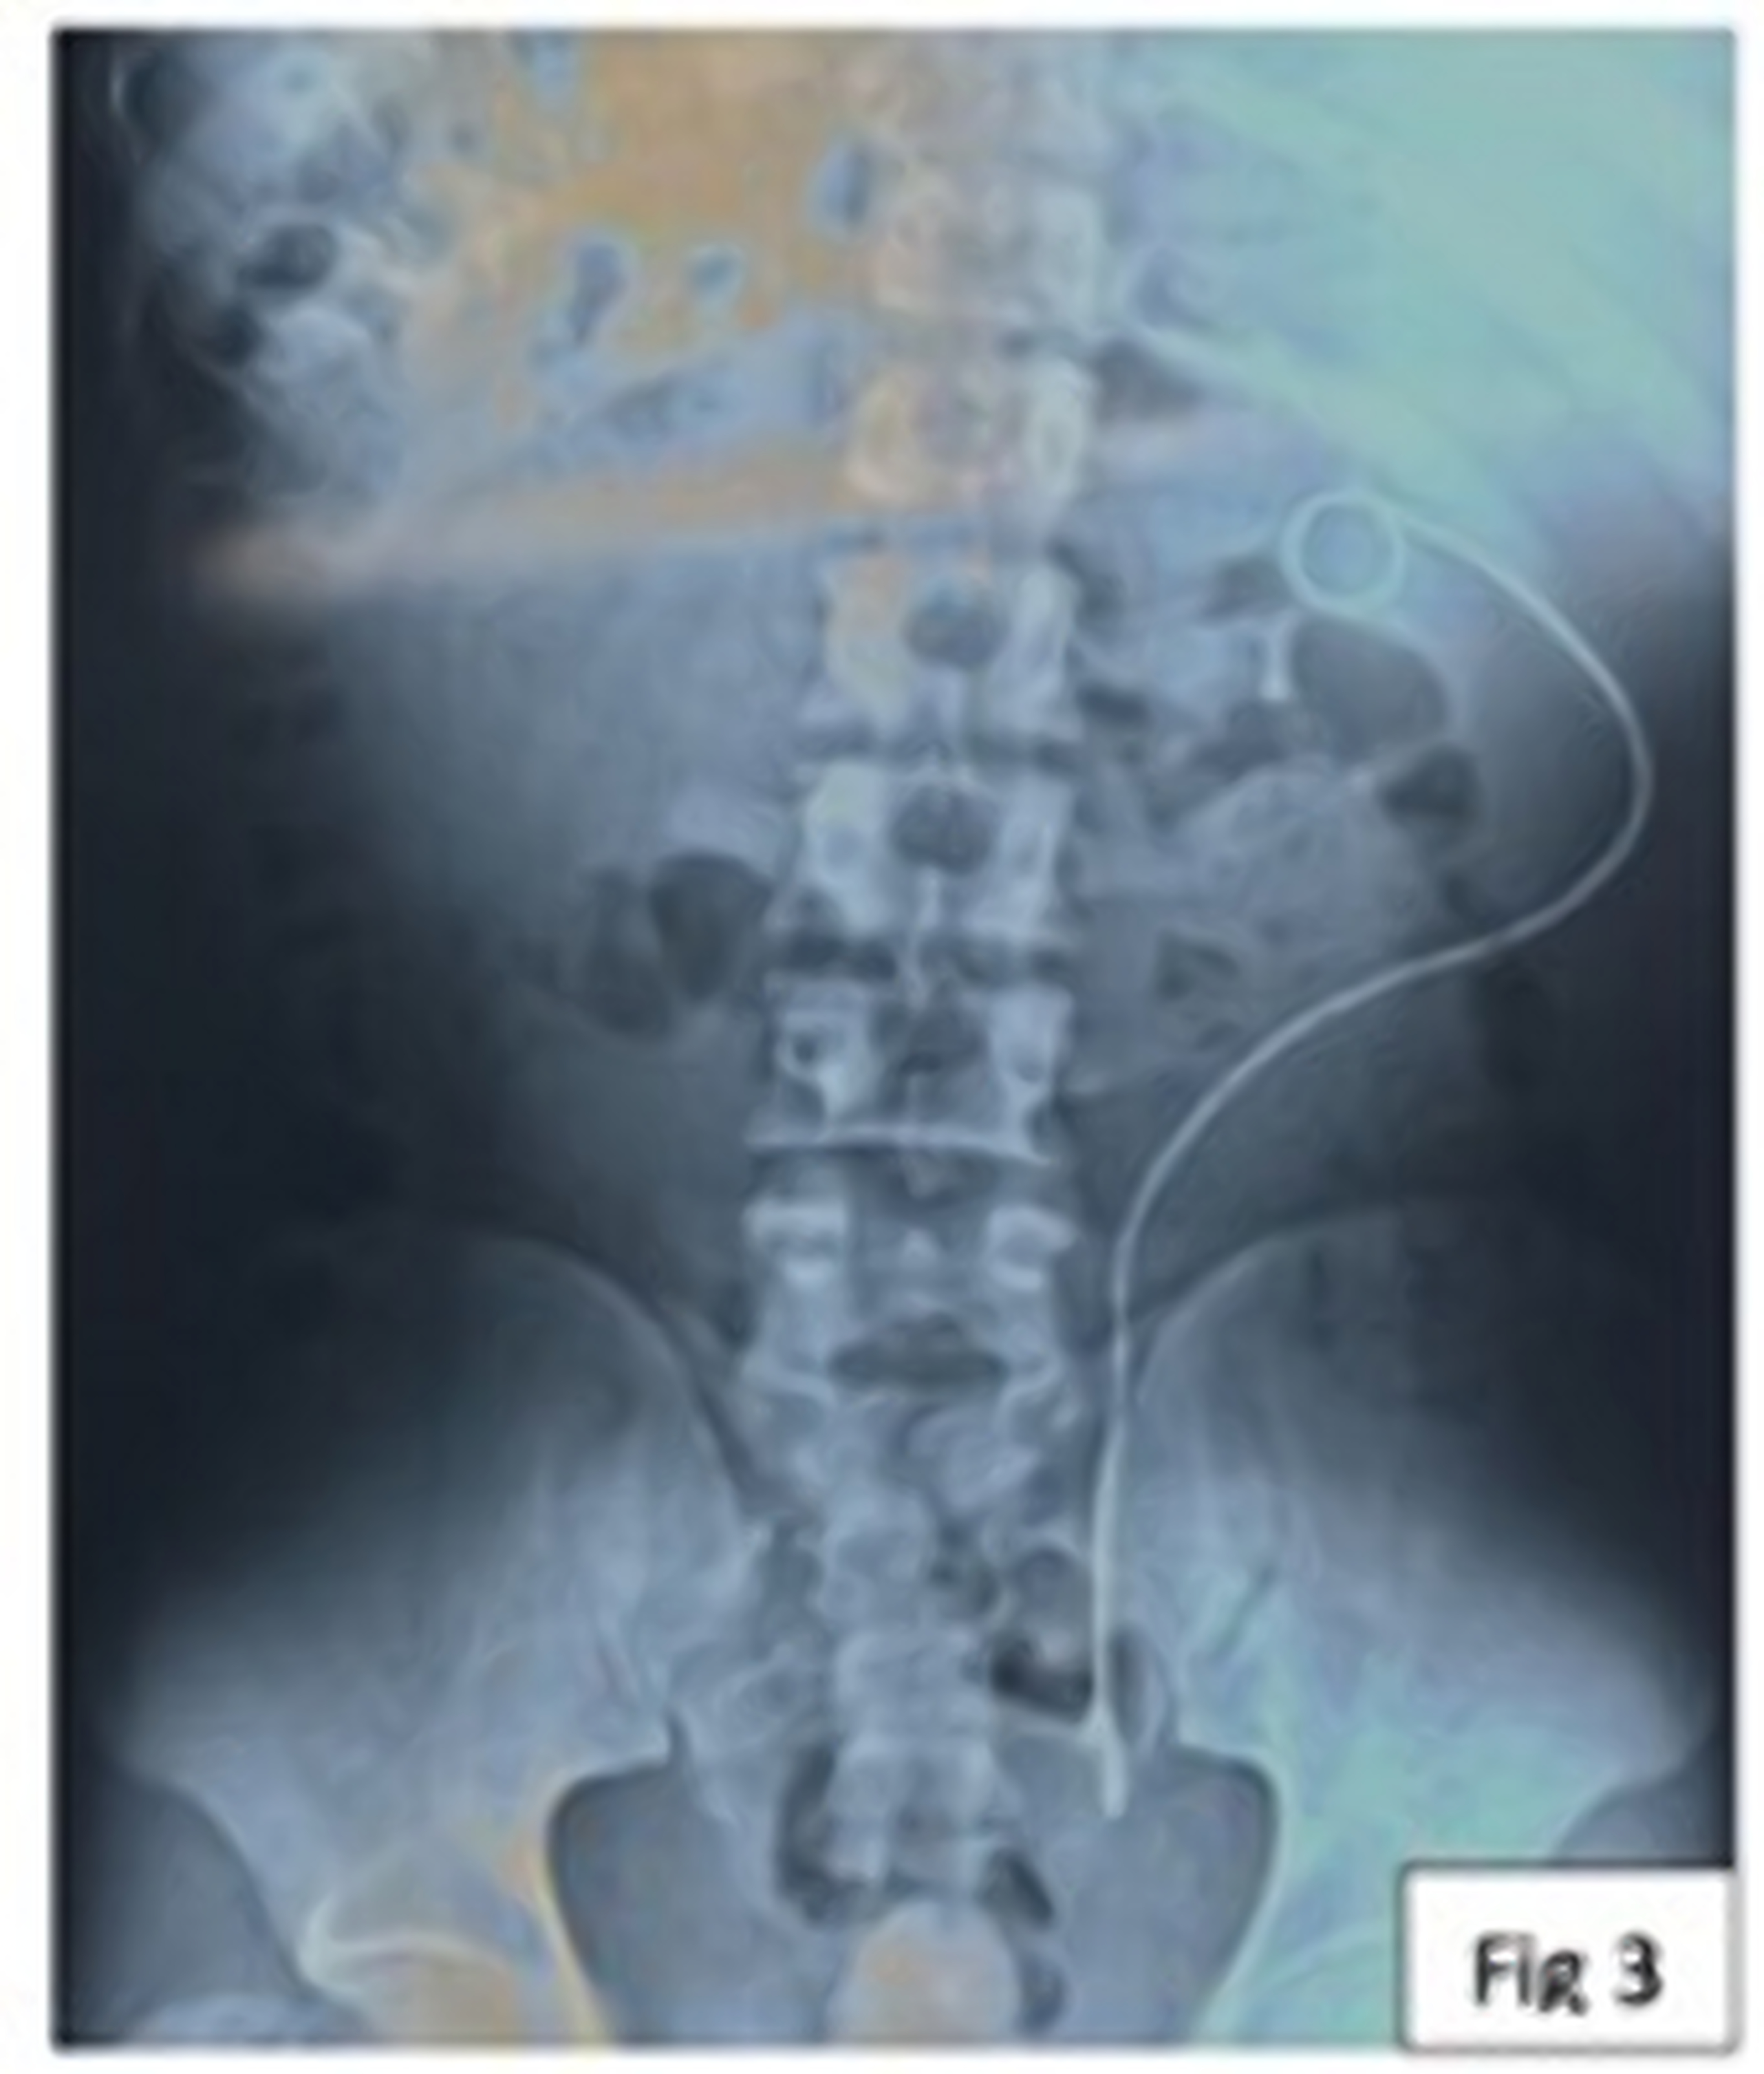

Case Series: Here we report proximal migration of DJ stent in three children with pelvi-ureteric junction (PUJ) obstruction treated with dismembered pyeloplasty. Ureteroscopy and retrieval of migrated DJ stents were performed in each of these patients.